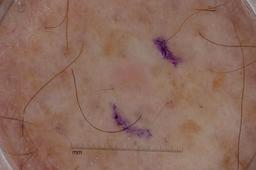

{

"age_approx": 70,

"anatom_site_general": "posterior torso",

"concomitant_biopsy": true,

"dermoscopic_type": "contact non-polarized",

"diagnosis_1": "Malignant",

"diagnosis_2": "Malignant melanocytic proliferations (Melanoma)",

"diagnosis_3": "Melanoma Invasive",

"diagnosis_confirm_type": "histopathology",

"image_type": "dermoscopic",

"lesion_id": "IL_1922786",

"melanocytic": true,

"sex": "male"